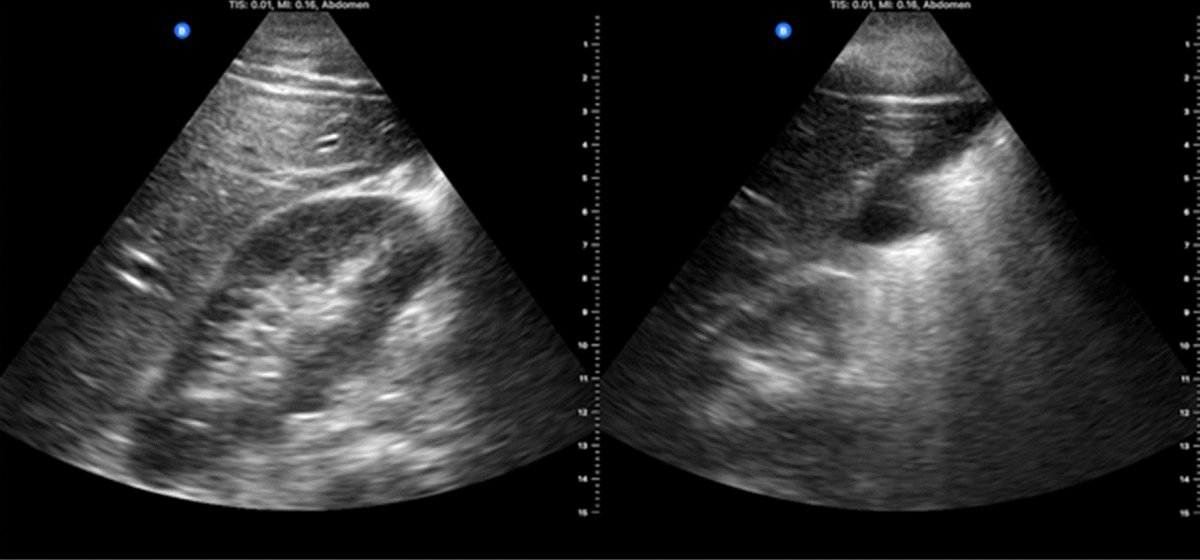

Ultrasound-guided preoperative skin-marking for deep inferior epigastric perforator flap surgery dlvr.it/TDdS6b